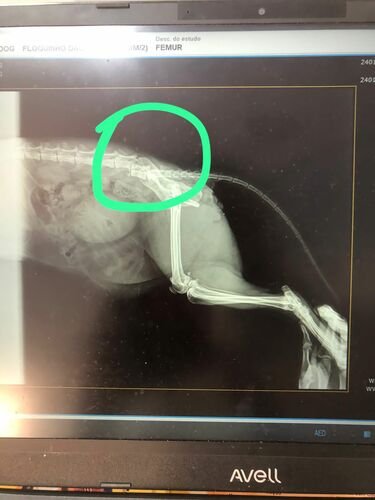

Nosso gatinho foi atropelado no dia 28/01 e está com uma luxação e fratura, sem movimentar as pernas e necessitando de internação para passagem de sonda e cirurgia com urgência.